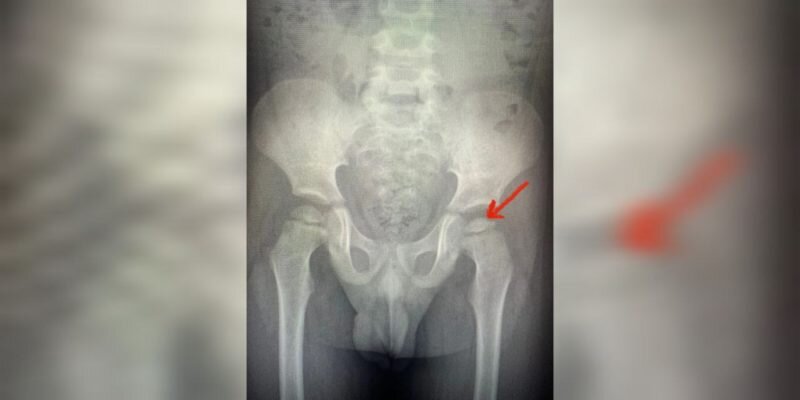

После осмотра ребенка врачи поставили ему предварительный диагноз «артрит левого тазобедренного сустава» или «болезнь Пертеса». После дополнительного обследования подтвердился второй вариант – потеря сферичности и снижение высоты головки левой бедренной кости.